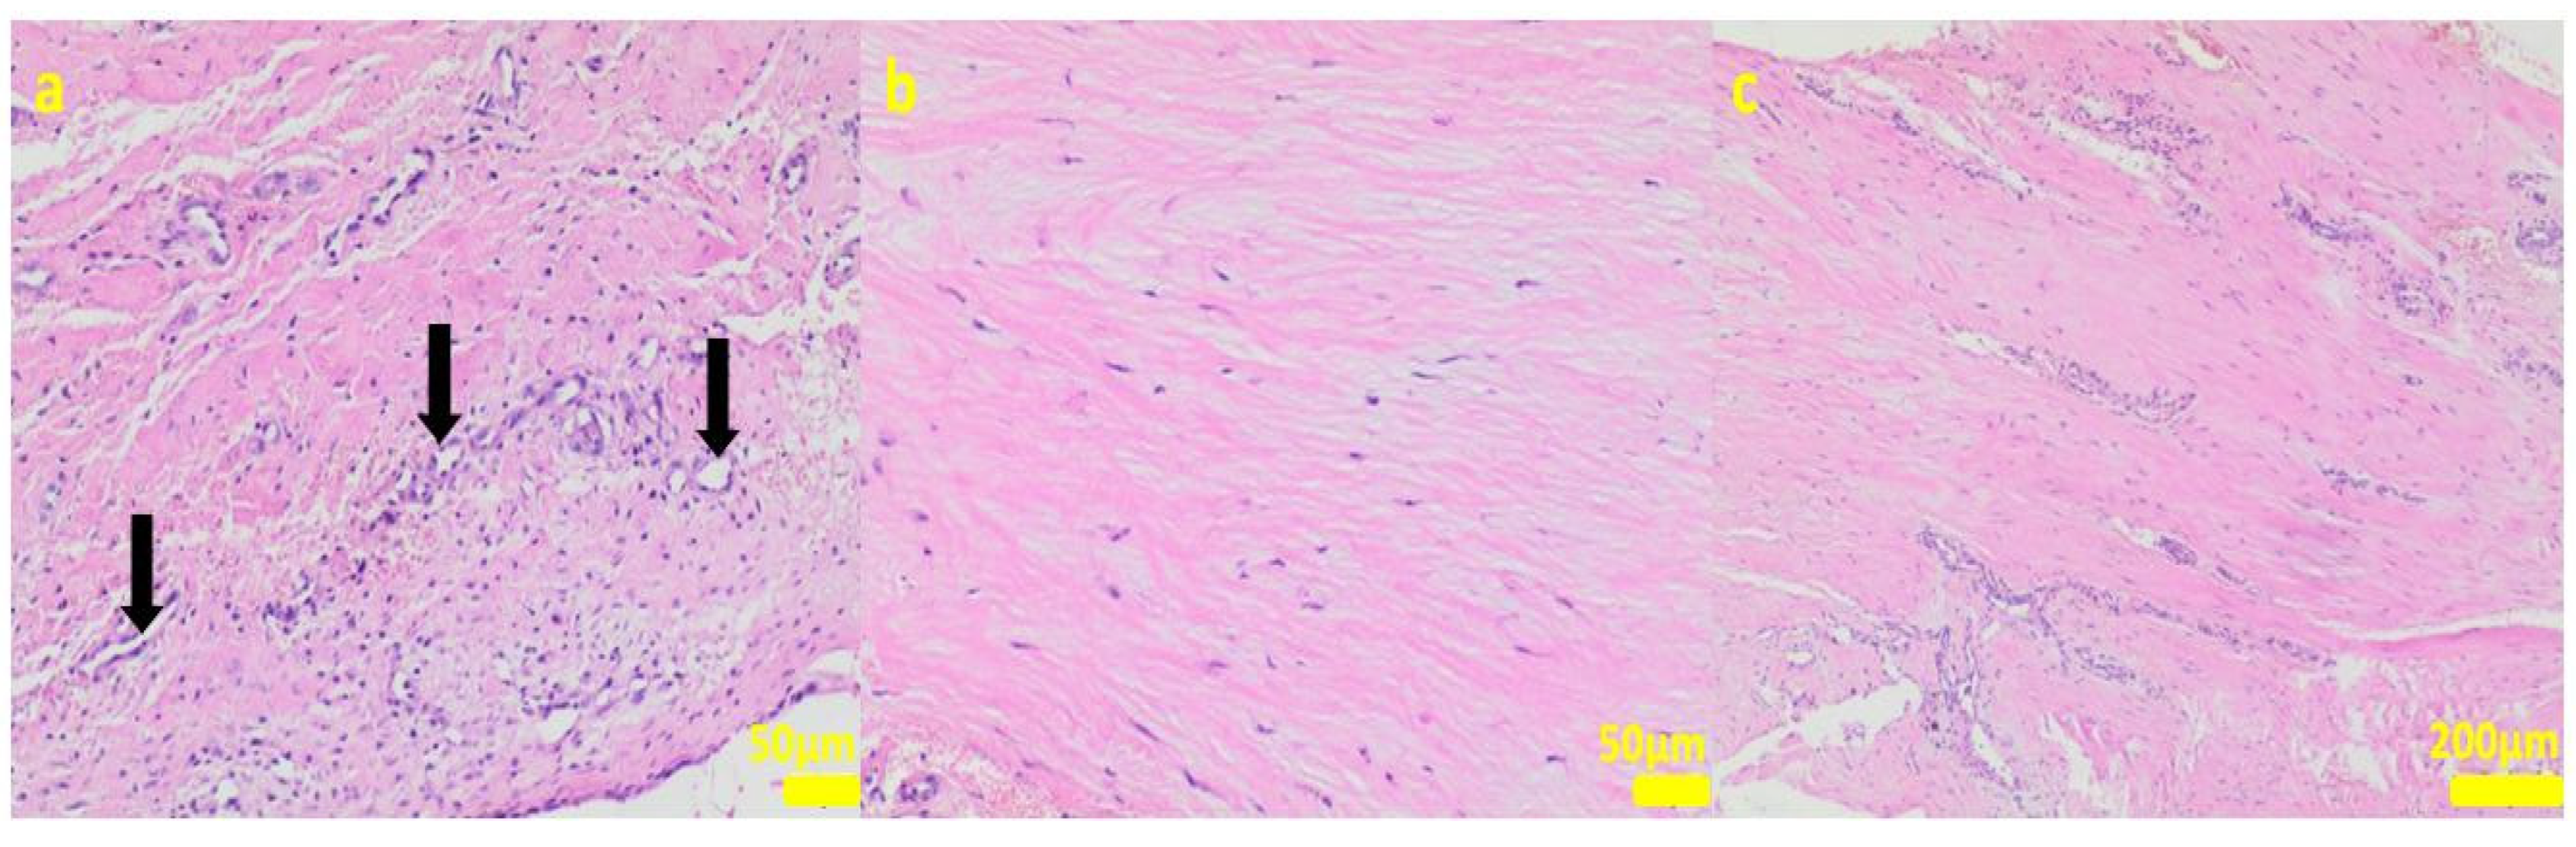

2.1. In Vitro Examinations

2.2. In Vivo Study

4.3. Cell Cultures